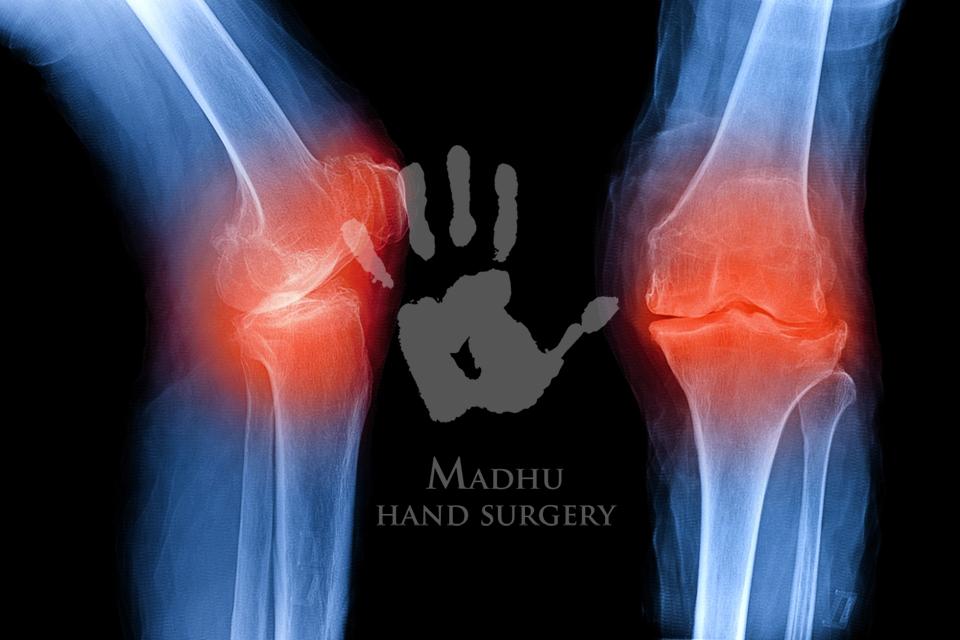

1. Osteoarthritis (Knee Joint Wear & Tear)

Osteoarthritis is the most frequent cause of chronic knee pain, especially in people above 40 years of age.

X-ray:

To detect fractures, arthritis, bone spurs, or joint space changes.